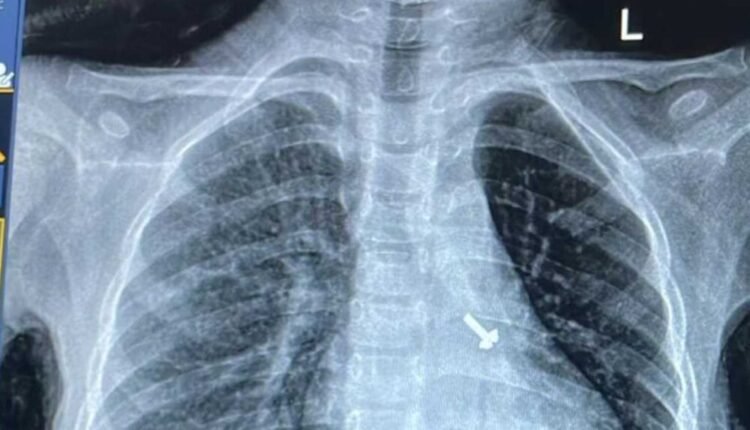

बालरोग विशेषज्ञ डॉ. व्यास कुमार राठौड़ के मुताबिक बच्चे की कुछ प्रारंभिक जांचें कराई गईं, जिसमें उसकी छाती के एक्स-रे एवं सीटी स्कैन में बच्चे के फेफड़े में एक पेंच दिखाई दिया है । इस विषय में चिकित्सक द्वारा बच्चे के अभिभावकों से पूछे जाने पर उन्हें बताया गया कि बच्चे ने घर में खेल-खेल में पेंच निगल लिया, जिसका पता परिजनों को नहीं लग पाया ।